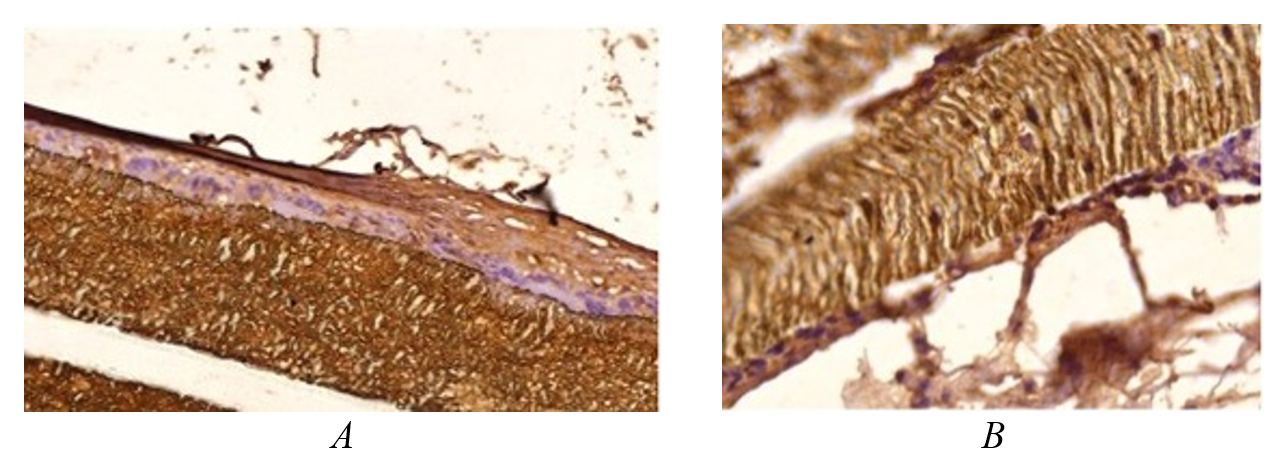

Figure 7 - 180 days after implantation of a polytetrafluoroethylene plate with a carbon coating:

A – tight adhesion of the implant to the connective tissue, the carbon coating layer is preserved as a narrow brown stripe; intact mast cells are indicated by arrows; B – section of the implant surface showing layers of immature collagen fibers of the forming capsule and surrounding abdominal wall tissues with bundles of mature collagen fibers (blue color); connective tissue does not grow into the thickness of the implant; between the capsule fibers and the implant surface, there are few small foreign body cells

Note: stained with Phenaf dye (A), mallory staining (B); Microphoto.×100